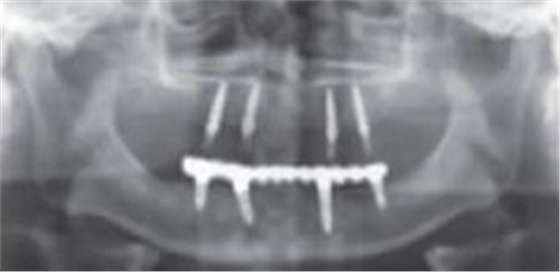

術后曲面斷層全景片(圖19)可見種植體在上頜位置較為理想,同時可見臨時義齒種植體開孔位置在13、23舌側、16、26牙合面近中,上下頜咬合關系理想。患者對種植臨時修復義齒滿意。

圖19 即刻修復后全景片

傳統(tǒng)導板一般是用熱壓膜技術制作的。首先應該給患者常規(guī)取模并灌注石膏模型,在石膏模型上根據患者咬合關系以及牙槽嵴的情況制作蠟型,然后再翻制石膏模型,繼而利用真空壓膜機制作樹脂薄膜導板,將導管放置種植體植入的理想位置并與導板結合一起。傳統(tǒng)導板制作方法簡單,價格便宜,在一定程度上考慮了種植修復后的效果和頜骨的解剖結構,但對于牙列缺失或骨量不足的情況下所提供的信息較為局限。本病例利用放射性模板獲得種植位點骨密度、可用骨的高度寬度以及種植體位置與重要解剖結構的位置關系等信息后將放射性模板的牙膠去除并進行消毒,戴入患者口內作為外科導板按照術前設計的種植位點用球鉆定位并在最佳骨質及骨量位置行種植手術,種植體都獲得較好的初期穩(wěn)定性,并行即刻修復。放射性模板在術中不能準確定向,本病例患者在制作即刻修復后可見臨時義齒種植體穿孔位置在近遠中方向跟術前設計幾乎一致。同時本病例在種植位置定位后采用微創(chuàng)切口,使患者術后腫脹及疼痛減少。將放射性模板作為種植簡易導板應用于上頜無牙頜種植修復,其效果好,價格便宜,術后并發(fā)癥小,是值得推薦的一種上頜無牙頜種植手術方案。